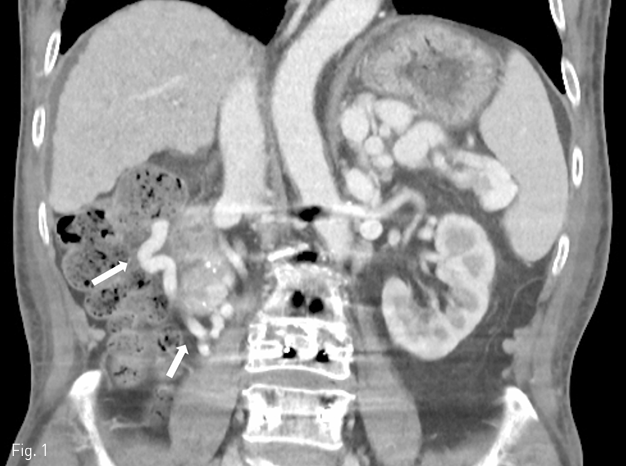

Fig 2B

(B) A venogram of duodenal varix shows leakage of contrast medium into duodenum (arrow), suggestive of active bleeding.